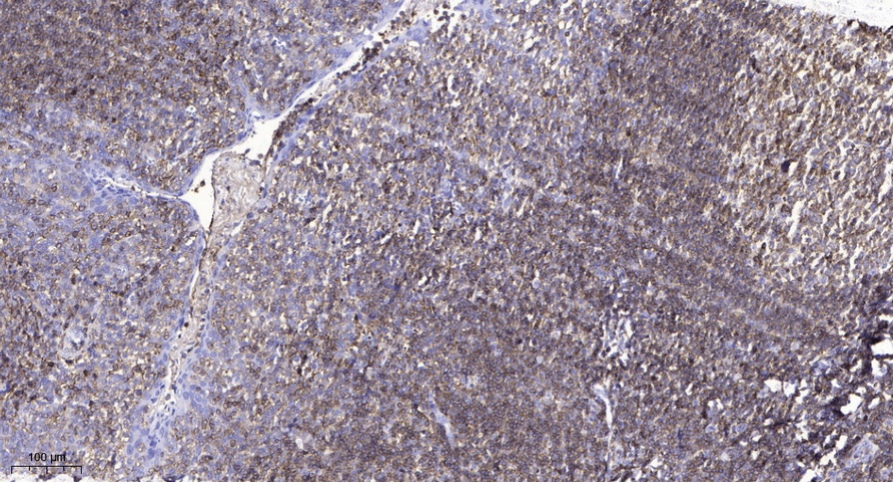

Immunohistochemical analysis of paraffin-embedded human tonsil. 1, Antibody was diluted at 1:200(4° overnight). 2, Tris-EDTA,pH9.0 was used for antigen retrieval. 3,Secondary antibody was diluted at 1:200(room temperature, 45min).